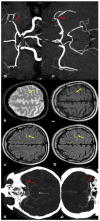

Spontaneous convexity subarachnoid hemorrhage (cSAH) is a vascular disease different from aneurysmal SAH in neuroimaging pattern, causes, and prognosis. Several causes might be considered in individual patients, with a limited value of the patient's age for discriminating among these causes. Cerebral amyloid angiopathy (CAA) is the most prevalent cause in people > 60 years, but reversible cerebral vasoconstriction syndrome (RCVS) has to be considered in young people. CAA gained attention in the last years, but the most known manifestation of cSAH in this context is constituted by transient focal neurological episodes (TFNEs). CAA might have an inflammatory side (CAA-related inflammation), whose diagnosis is relevant due to the efficacy of immunosuppression in resolving essudation. Other causes are hemodynamic stenosis or occlusion in extracranial and intracranial arteries, infective endocarditis (with or without intracranial infectious aneurysms), primary central nervous system angiitis, cerebral venous thrombosis, and rarer diseases. The diagnostic work-up is fundamental for an etiological diagnosis and includes neuroimaging techniques, nuclear medicine techniques, and lumbar puncture. The correct diagnosis is the first step for choosing the most effective and appropriate treatment.